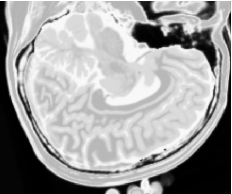

As figuras 2 (banda 0), 3 (banda 1) e 4 (banda 2) mostram a fatia 97 de um volume de imagens sagitais com 181 fatias e 0% de ruído, ponderadas em PD (densidade de próton), T1subscript𝑇1T_{1} e T2subscript𝑇2T_{2}, enquanto a figura 5 ilustra a composição colorida R0-G1-B2 da mesma fatia. Pode-se notar no topo do crânio, na parte inferior das imagens, a presença de artefatos, que podem ser resultantes de erros no simulador, mas que não são prejudiciais à análise, uma vez que, neste trabalho, não é dada ênfase à análise anatômica.

Figura 2: Imagem de RM da fatia 97 ponderada em PD

Refer to caption